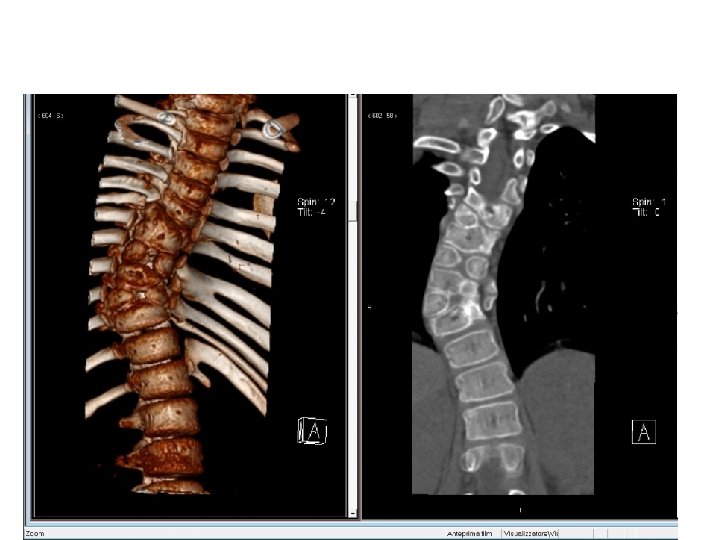

N. R. a 8

N. R. 8 a 10 m N. R. 9 a 10 m